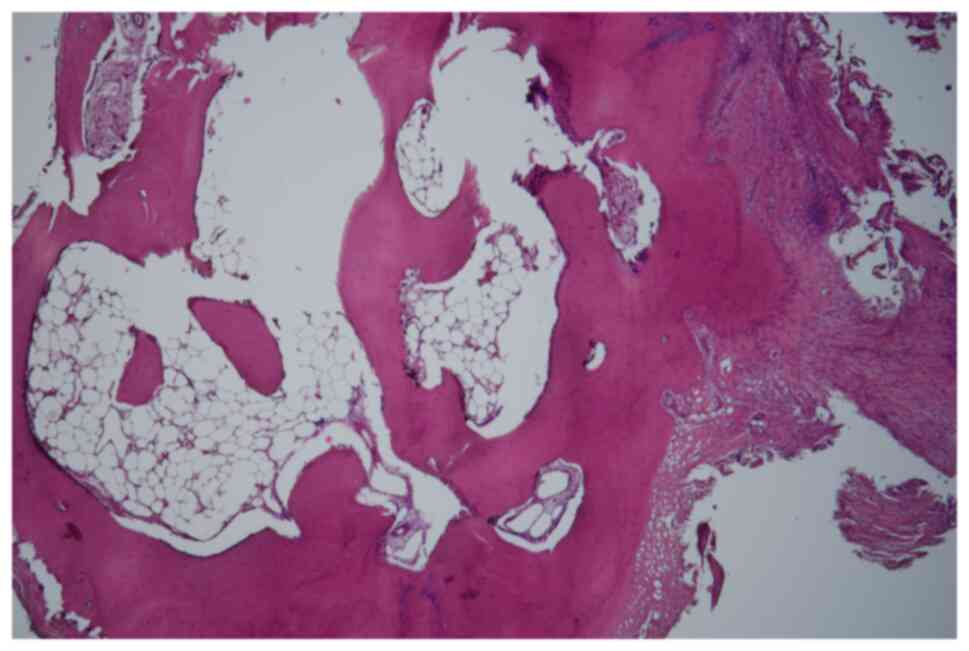

In June 2007, a 50-year-old male presented to the Masaryk Memorial Cancer Institute Sarcoma Center, with a 1-month history of persistent pain in the right ankle. Further investigations showed a cystic lesion of the talus on a CR scan, which was later confirmed by a supplementary CT scan (Fig. 16). The histopathology report diagnosed GCTB with a secondary aneurysmal cyst of the talus (Fig. 17), leading to a recommendation for intralesional resection with bone cement augmentation. After receiving the recommended treatment, the patient returned 5 months later with swelling and increased pain in the ankle. A follow-up CT scan showed destruction of the bone surrounding the bone cement, as well as osteolysis of the calcaneus and the presence of an extraosseous mass proximally (Figs. 16 and 18). Due to the extent of osteolysis, the patient required an astragalectomy. Subsequent histopathology reports showed a diagnosis of giant-cell rich osteosarcoma, contradicting the initial findings (Fig. 19). Further staging scans indicated the presence of lung metastases (Fig. 20). The Musculoskeletal Tumor Committee recommended metastasectomy followed by adjuvant CHT. Despite the successful removal of 12 lung metastases, the patient developed additional lung metastases within two months. Despite palliative care efforts, the patient died 6 months later.

Case 4. Hematoxylin and eosin staining of the resected talus. Magnification, ×100. A highly cellular malignancy was shown characterized by eosinophilic lace-like osteoid interwoven with numerous giant multinucleated cells, consistent with giant cell-rich osteosarcoma.